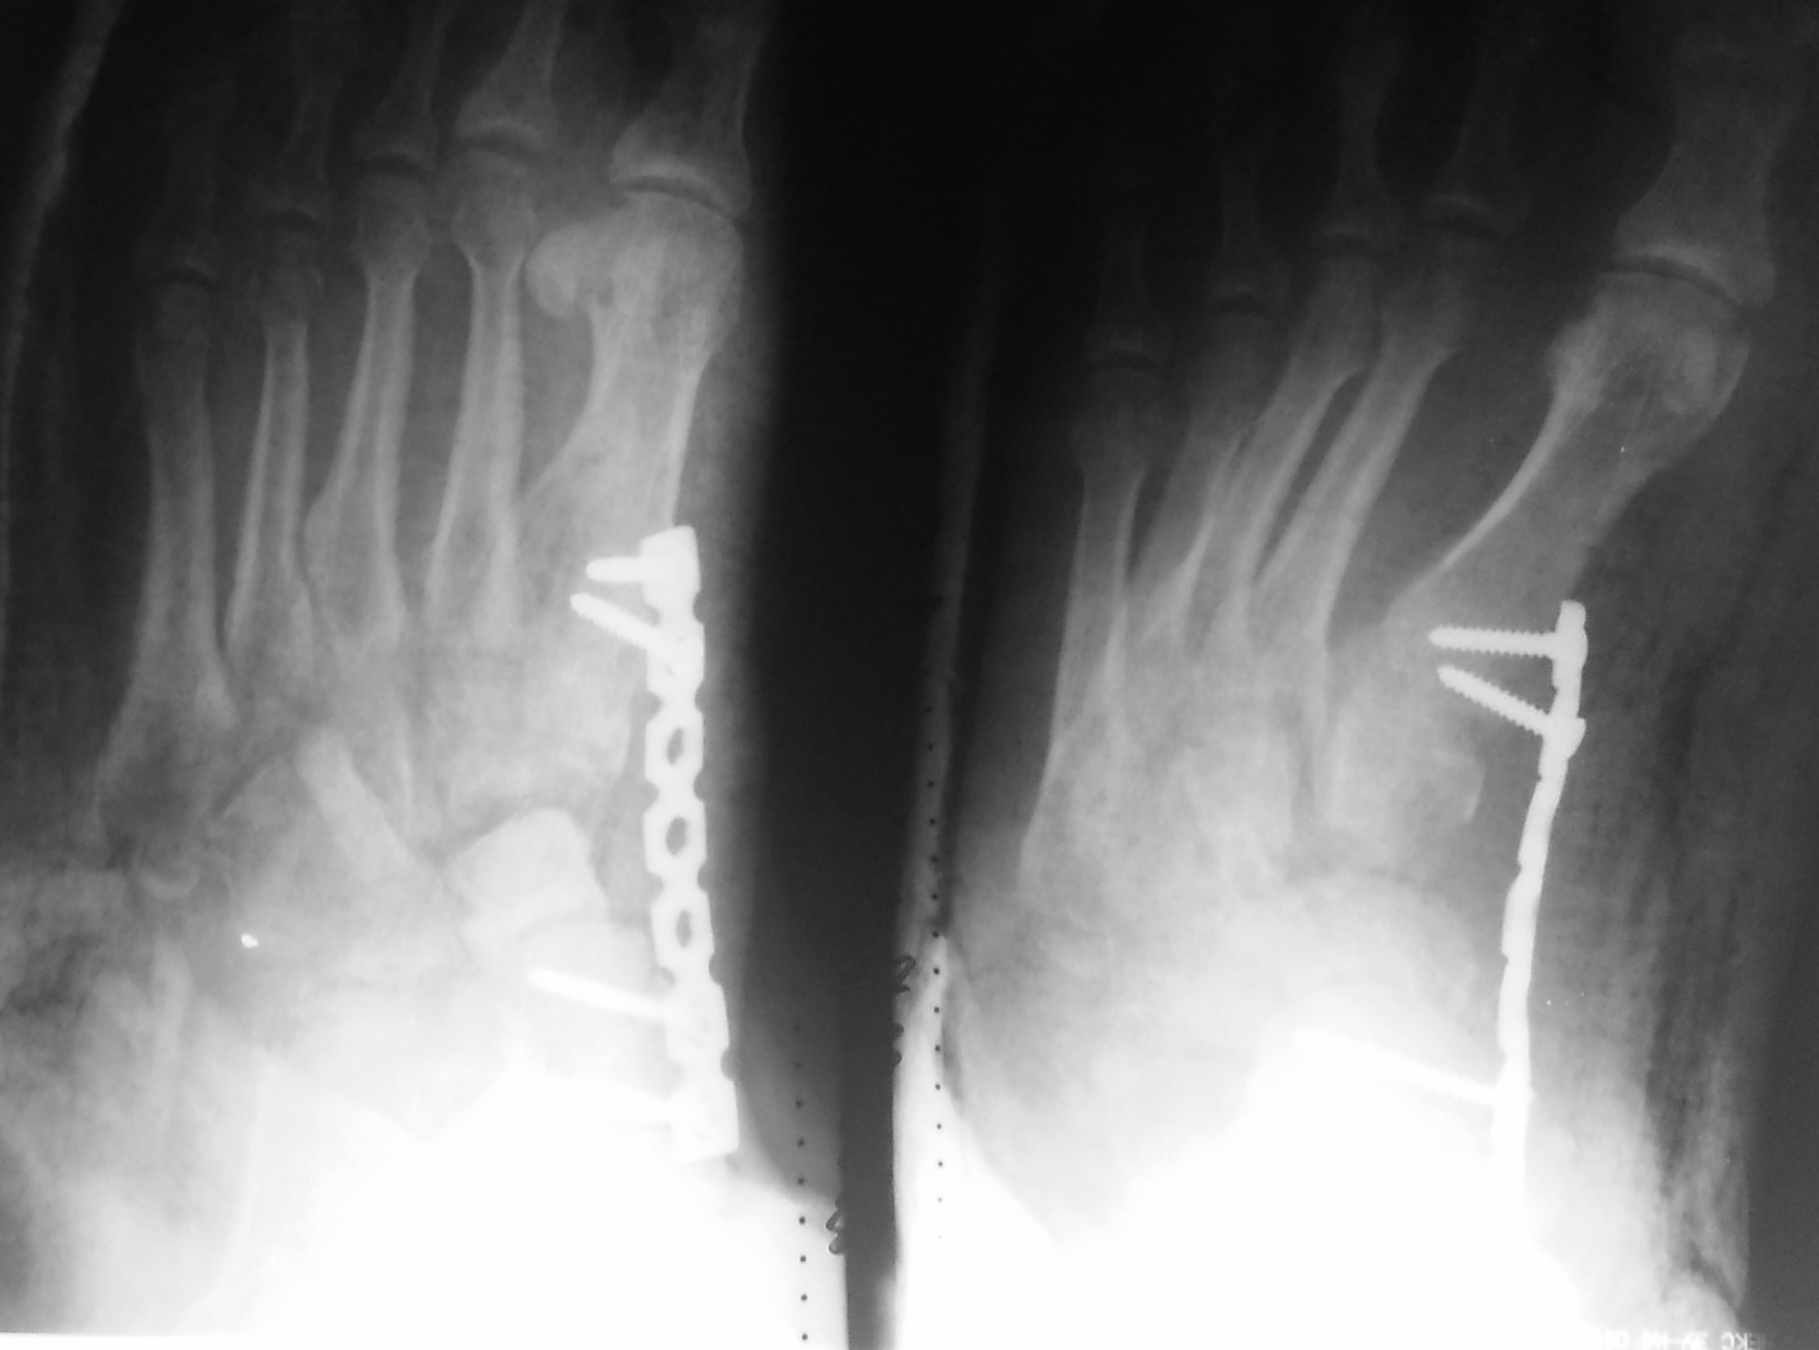

[Ortho] застарелый переломовывих в суставе Шопара

как-то так, извиняюсь за снимки, дистрактор все же пригодился, проблем с

вправлением не было.  На предыдущие вопросы, травма - по ноге проехал

УАЗ, не курит, не злоупотребляет.